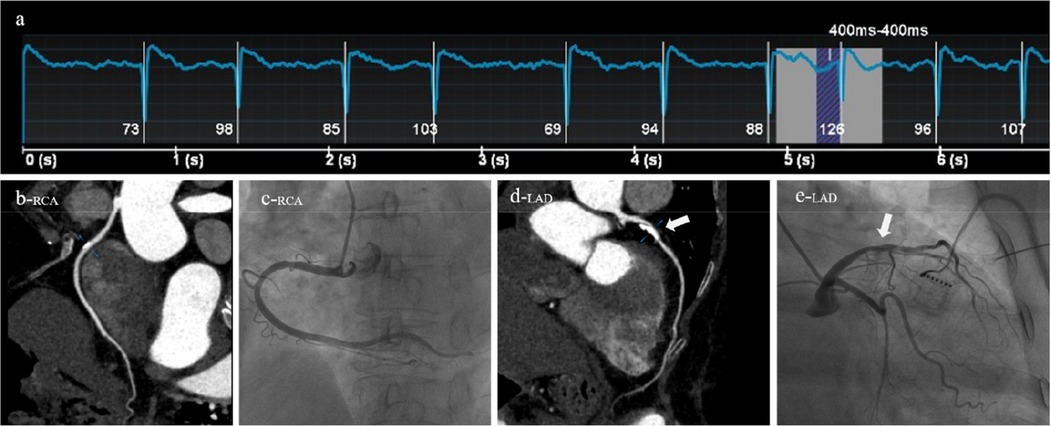

Figure 3

A 64-year-old female patient was clinically diagnosed with atrial fibrillation and arrhythmia. Both CT (AI-ADS, AI-ADS + radiologist) and ICA showed moderate stenoses of the sixth segment of the left anterior descending coronary artery, (a) ECG showed a heart rate of 96 beats/min and heart rate variability of 28 beats/min during the scan, (b) right coronary artery, CPR, (c) right coronary artery, ICA, (d) left anterior descending coronary artery, CPR, (e) left anterior descending coronary artery, ICA.